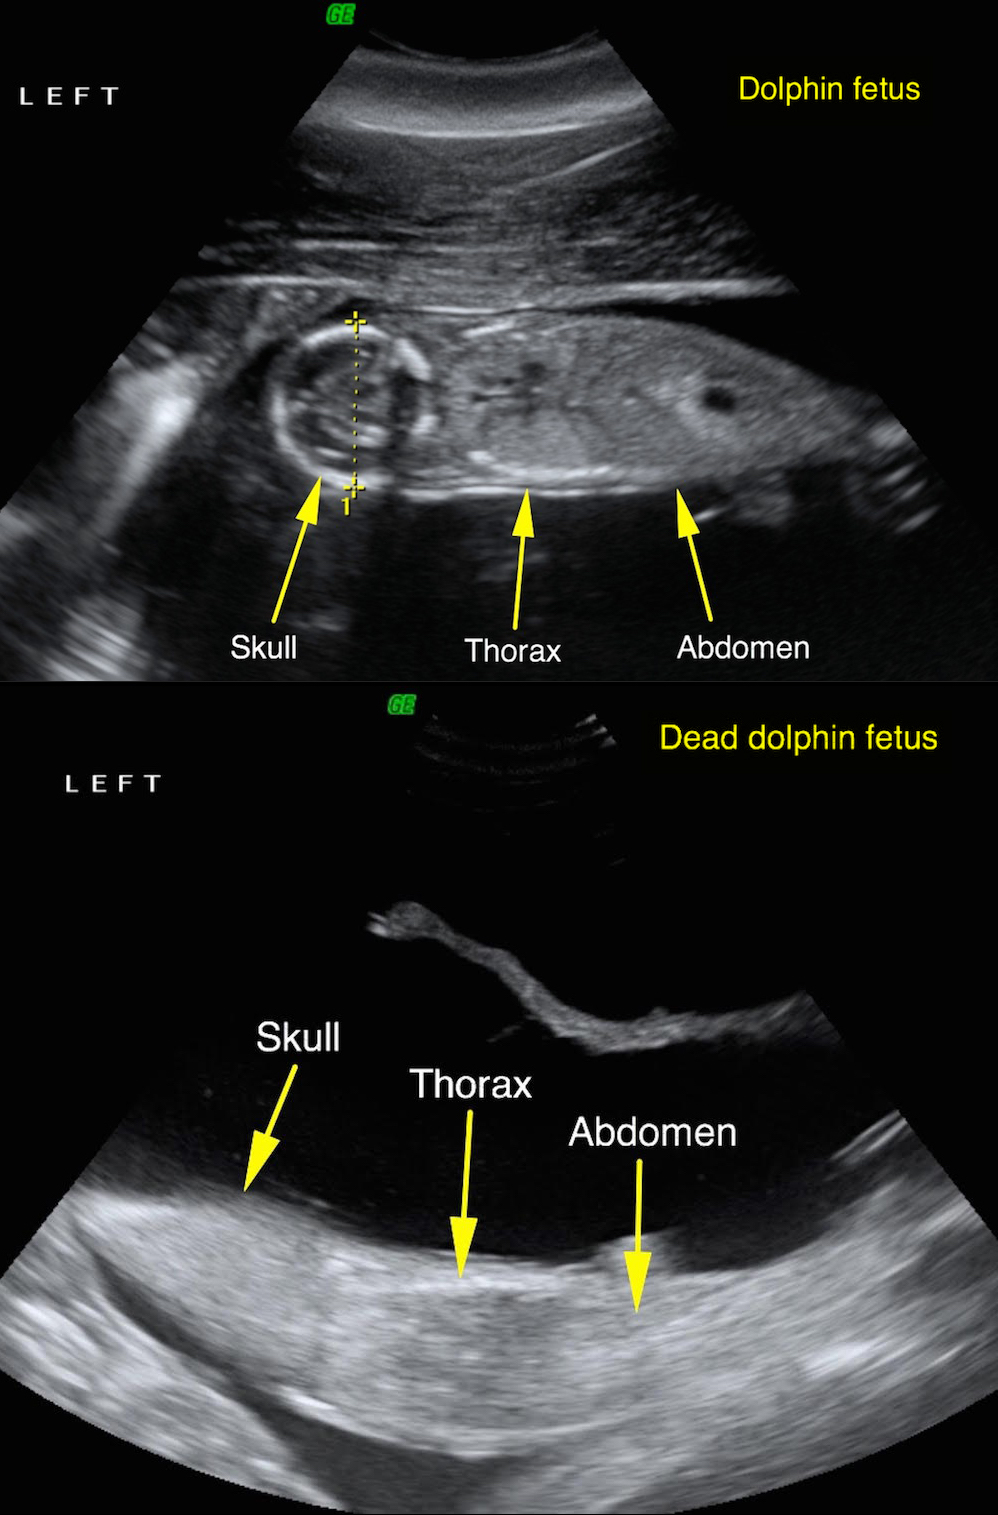

Ultrasounds of a living dolphin fetus (top) and a nonviable fetus (bottom), both taken during August 2011. Researchers later saw the female with the viable fetus swimming with a calf in 2012.

In March 2013, researchers saw the female dolphin known as Y01 pushing a dead calf in waters affected by the Deepwater Horizon oil spill. This behavior is sometimes seen in females when their newborn calves do not survive.